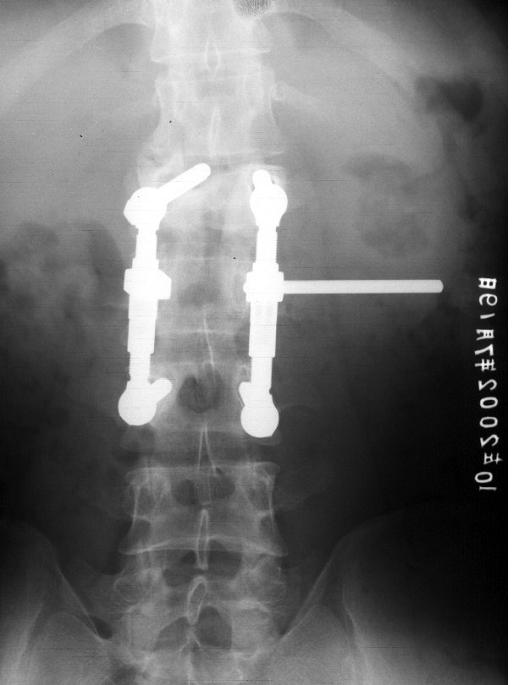

开放手术一般用于年轻人,骨质比较好的病人。骨折后出现明显的后突畸形需要矫正,手术进行复位,内固定,一般骨折愈合后建议取出内固定。否则容易出现松动、断钉的并发症。

脊柱内固定后出现松动